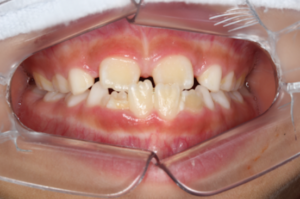

反対咬合(受け口)の症例

治療途中の小児矯正の症例です。

成長期に上顎の幅を広げることで、骨格的なバランスを整え、受け口の改善を図りました。

現在は、マウスピース矯正で歯の細かな位置を調整し、より安定した噛み合わせを目指しています。

反対咬合(受け口) |

6歳 男性 |

2年経過(治療継続中) |

¥450,000(税別) |